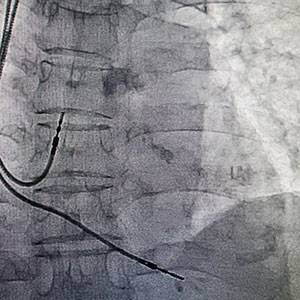

Рентген-ангиографическая установка Siemens Artis ZeeУниверсальная ангиографическая установка напольного исполнения для общей ангиографии, нейрорадиологии, кардиологии и интервенциональной терапии.

Полностью цифровая система изображений с плоским детектором высокого разрешения.

Система с одноплановой С-дугой для цифровой съемки, отвечающая современным требованиям проведения ангиографических и интервенционных процедур.